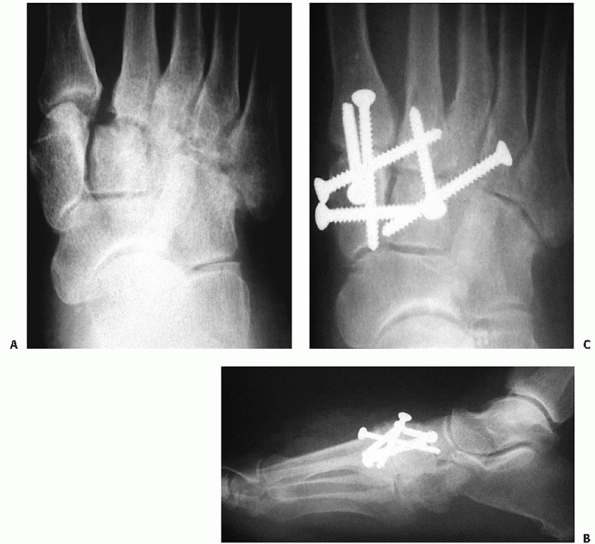

![]() |

FIGURE 60-11 Neuropathic dislocation of the navicular. A. Anteroposterior radiograph with medial deviation of the navicular. B. Lateral radiograph showing plantar migration. C,D. Fixation post reduction for fusion of the naviculocuneiform joints.